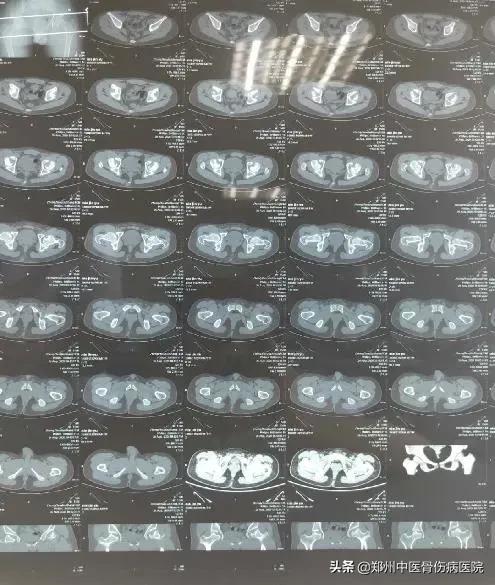

发生在髋关节的剥脱性骨软骨炎:

聂先生,男,19岁,河南新乡人。主诉:双髋间断性疼痛4年6个月。2015年7月到延津县某医院摄双髋CT:双侧股骨头缺血性坏死可能性大。2018年08月第1次住院治疗。

自诉双髋疼痛不重,查体功能活动尚可。舌质红,苔薄黄。脉滑数。患者个子不高,智力正常。

腰椎椎体呈“*弹子**头”样改变。双侧腹股沟中点无压痛,双髋关节活动尚可,双“4”字试验阳性,下蹲可。

家族中无类似疾病发生。经服药治疗3年余,缺损的骨质得到新生骨质的填充,患者弃拐行走。